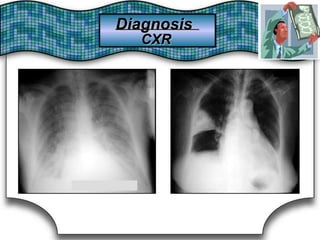

Chest X Ray (CXR)X Ray (CXR)Chest

Chest RadiographRadiographChest Suggestive DiagnosisSuggestive Diagnosis

Cardiomegaly, increasedincreasedCardiomegaly,

pulmonary vascular distributiondistributionpulmonary vascular

Chronic heartheart failure,failure, mitralmitral valve stenosisvalve stenosisChronic

Cavitary lesionsCavitary lesions Lung abscess, TB,TB, necrotizing carcinomanecrotizing carcinomaLung abscess,

Diffuse alveolar infiltratesinfiltratesDiffuse alveolar Chronic heartheart failure,failure, pulmonary edema,pulmonary edema, aspirationaspirationChronic

Hilar adenopathy oradenopathy or massmassHilar Carcinoma, metastaticmetastatic disease,disease, infectioninfectionCarcinoma,

HyperinflationHyperinflation COPDCOPD

Lobar oror segmentalsegmental infiltratesinfiltratesLobar Pneumonia, thromboembolism, obstructing carcinomathromboembolism, obstructing carcinomaPneumonia,

Mass lesion,lesion, nodules,nodules, granulomasgranulomasMass

Carcinoma,

granulomatosis,

metastatic disease, Wegener's

vasculitides

Carcinoma, metastatic disease, Wegener's

septic embolism,granulomatosis, septic embolism, vasculitides

Patchy alveolar infiltratesinfiltratesPatchy alveolar

Bleeding disorders, idiopathic pulmonaryBleeding disorders, idiopathic pulmonary

hemosiderosis, Goodpasture's syndromesyndromehemosiderosis, Goodpasture's